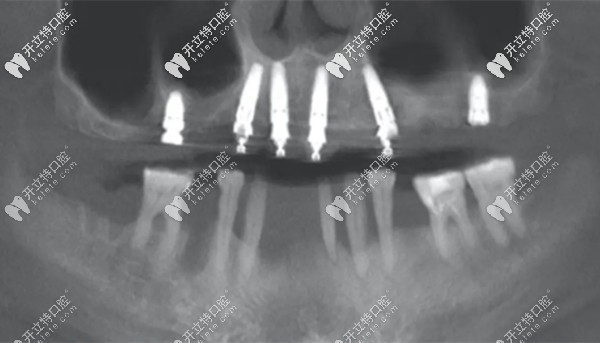

但,上/下頜各植入6顆牙根的全口種植牙,不是都叫all-on-6即刻種植牙哦~它也可以是以點(diǎn)種的方式來植入,就如下圖所示? ?↓

點(diǎn)種6顆種植體

(上頜點(diǎn)種六顆種植體)

能看懂么?這張全景片中的上頜六顆種植體,就是“點(diǎn)種”技術(shù)。分別選取牙槽骨量較為充沛的部位,將牙根種入。

兩側(cè)后牙可以明顯看出,用的是較短的種植體,這樣的好處是可以避免植骨手術(shù)。